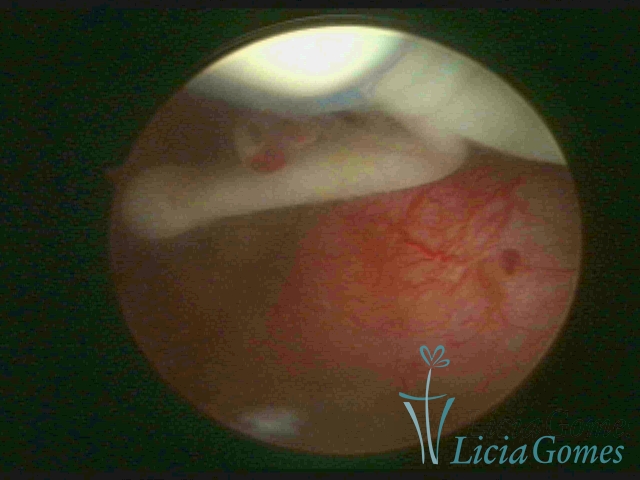

Cavidade uterina com endoceptivo tipo Mirena®, envolto em secreção purulenta

×